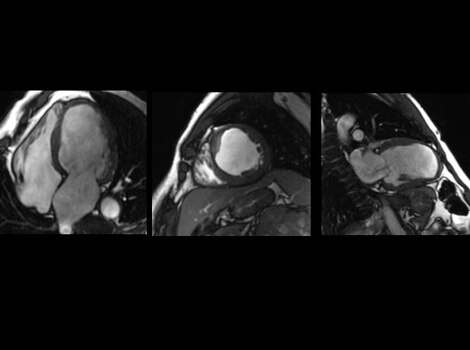

SIGNA Works CV 成像与分析工具

通过一个自由呼吸,心脏 MR 即可评估出心脏形态、功能、血流、组织活力和冠状动脉解剖结构,而无电离辐射危害。 了解更多信息

无创心脏 MR 用于评估心脏形态、功能、血流、组织活力和冠状动脉解剖结构,而无电离辐射危害。了解更多信息

SIGNA™ Works CV 成像与分析工具